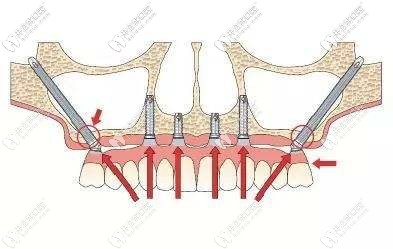

深圳登緹斯口腔的醫(yī)生考慮到我對(duì)傳統(tǒng)種植牙技術(shù)的擔(dān)憂,就對(duì)我的牙槽骨情況做了詳細(xì)分析,建議上頜采用雙側(cè)穿顴穿翼板種植、即刻修復(fù)即刻負(fù)重技術(shù),不用植骨、縮短療程;下頜采用即拔即種的即刻負(fù)重種植技術(shù)。

深圳登緹斯口腔的醫(yī)生還介紹了什么是穿翼板種植牙技術(shù):

穿翼板穿顴種植適用上頜骨萎縮,做常規(guī)種植牙需要植骨、做內(nèi)外提升的無(wú)牙頜顧客;而且此技術(shù)無(wú)需全麻、手術(shù)不翻瓣、創(chuàng)傷小、術(shù)后腫脹和疼痛也非常輕。